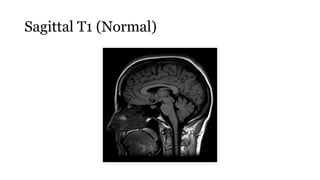

T1

• Provides the most anatomically-relevant images

• Fluid (in CSF and orbits) is dark

• Grey matter is darker than the white matter

Sagittal T1 (Normal)

T1 • Provides themost anatomically-relevant images • Fluid (in CSF and orbits) is dark • Grey matter is darker than the white matter